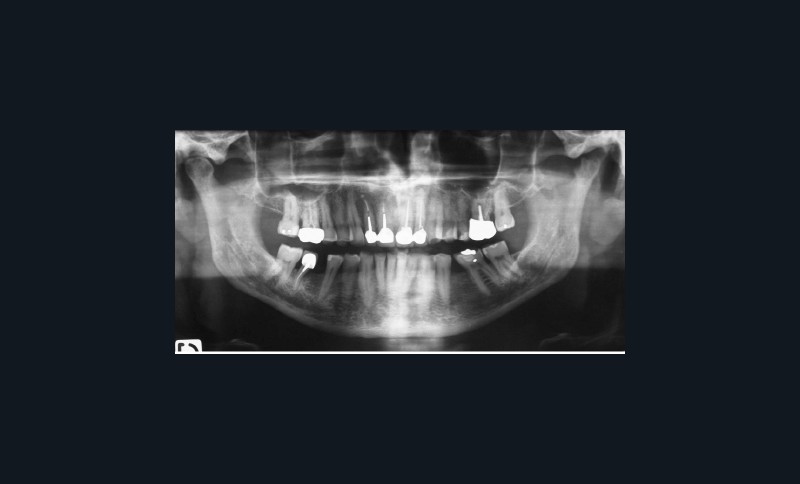

Algie ancienne de l’ATM gauche, sensation d’ouverture limitée et déviée à droite.

La cinématique mandibulaire est légèrement limitée (41 mm), défléchie à droite.

Muscles : muscles élévateurs non hypertrophiques, mais hyperdenses.

Douleur : algie ATM gauche provoquée à l’étirement.

ATM : atteinte dégénérative de l’ATM gauche éventuellement en évolution.

Dents : soins dentaires à réaliser sur 16, 26, 37.

Amputation mésiale de 46 ?, légères érosions.

Bruxisme : net avec attrition antérieure marquée en particulier en regard des coiffes céramiques.

Occlusion : décentrage gauche, création d’une légère béance antérieure probable conséquence

de l’atteinte de l’ATM gauche.